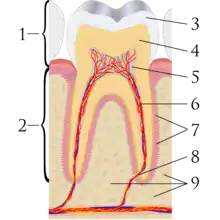

A tooth is composed of an outer shell of calcified hard tissues (from hardest to softest: enamel, dentin, and cementum), and an inner soft tissue core (the pulp system), which contains nerves and blood vessels. The visible parts of the teeth in the mouth – the crowns (covered by enamel) – are anchored into the bone by the roots (covered by cementum). Underneath the cementum and enamel layers, dentin forms the bulk of the tooth and surrounds the pulp system. The part of the pulp inside the crown is the pulp chamber, and the central soft tissue nutrient canals within each root are root canals, exiting through one or more holes at the root end (apical foramen/foramina). The periodontal ligament connects the roots to the bony socket. The gingiva covers the alveolar processes, the tooth-bearing arches of the jaws.[42]: 1–5

Enamel is not a vital tissue, as it lacks blood vessels, nerves, and living cells.[18] Consequently, pathologic processes involving only enamel, such as shallow cavities or cracks, tend to be painless.[18] Dentin contains many microscopic tubes containing fluid and the processes of odontoblast cells, which communicate with the pulp. Mechanical, osmotic, or other stimuli cause movement of this fluid, triggering nerves in the pulp (the "hydrodynamic theory" of pulp sensitivity).[19] Due to the close relationship between dentin and pulp, they are frequently considered together as the dentin-pulp complex.[43]: 118